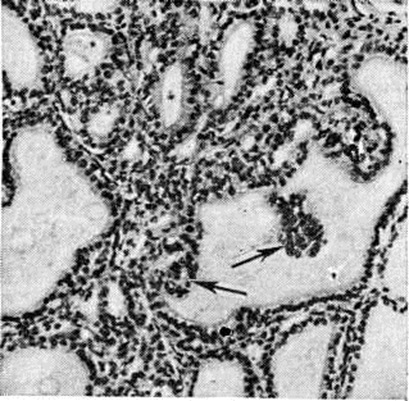

Рис. 1.

Микропрепарат щиторицной железы при эндемическом парен иуттозном зобе: диффузная интрафолликулярная пролиферация эпителия; сосочковидные выпячивания эпителия в полость фолликула (указаны стрелками); окраска гематоксилин-эозином; × 75.

Патологическая анатомия характеризуется наличием трёх морфологический форм Зоб эндемический: разлитой (диффузной), узловой (нодозной) и смешанной (диффузно-узловой). В начале заболевания наблюдается диффузная форма с равномерным увеличением железы при неизменённых её контурах. Образование отдельных центров пролиферации приводит к развитию узловой или смешанной формы зоба. При узловой гиперплазии иногда обнаруживаются множественные узлы, различные по форме, плохо отграниченные от окружающей ткани, но сохраняющие тенденцию к росту. Микроскопически Зоб эндемический гетерогенен. Диффузный зоб представлен нормальной или микрофолликулярной тканью. В зависимости от функционального состояния фолликулы содержат базофильный, «густой» или только просвечивающий, почти прозрачный эозинофильный коллоид. В покое эпителий фолликулов кубический или плоский; в состоянии функциональной активности он становится высоким, светлым, образует сосочковидные выпячивания в полость фолликула (рисунок 1). В диффузных и узловых зобах встречаются трабекулярные и тубулярные структуры. Предполагается, что чем тяжелее эндемия зоба, тем чаще встречаются малодифференцированные формы паренхиматозного зоба (тубулярная и трабекулярная). Коллоидный зоб построен из фолликулов различной величины (макро и микрофолликулярный), богатых коллоидом, дающим положительную реакцию на РНК, белки и мукополисахариды. Комбинация фолликулов различной величины создаёт пёструю картину коллоидного зоба (рисунок 2 и 3). В зобах могут обнаруживаться инволюционные изменения (кровоизлияния, дистрофические процессы) с дальнейшим отложением в изменённых участках извести и холестерина. Паренхиматозные и коллоидные формы зоба могут трансформироваться в фиброзную форму с увеличением соединительнотканных образований. Солитарные аденомы (узлы) быстрее подвергаются различным инволюционным изменениям в связи с особым типом кровообращения. Узловой зоб может подвергаться малигнизации. Хотя нет достаточно убедительных данных о том, что Зоб эндемический чаще малигнизируется по сравнению со спорадическим, однако солитарная аденома в условиях эндемии зоба рассматривается как проблема онкологическая.